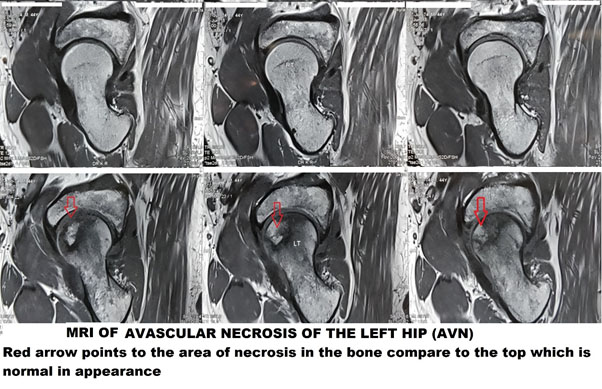

The primary investigation remains plain x rays. They demonstrate advanced stages quite clearly. In cases of a high index of suspicion and an ordinary-looking x-ray, MRI is the investigation of choice. It demonstrates the stage of the disease and thus guides treatment as well.